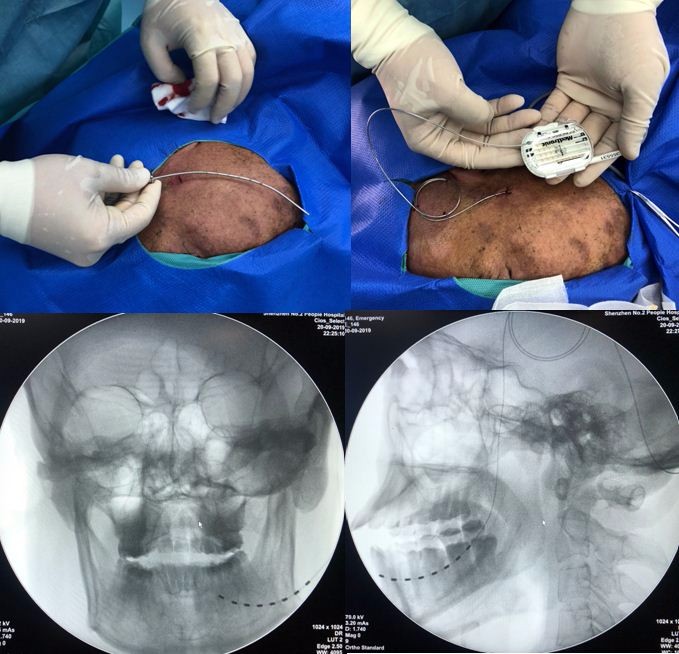

经过细致充分的准备,蔡晓东主任、张豆豆主治医师在2019年9月20日成功实施了该手术。手术在局麻下进行,通过耳前一个小切口穿刺将刺激电极放置在下颌神经的支配区域,外接电池测试时电极释放微弱的电流产生的酥麻的感觉可以完全覆盖下颌疼痛区域,术中老王就觉得舒服多了,疼痛感觉完全消失了。团队将术中照片及手术效果告知Tipu教授后,Tipu教授兴奋地回复到" Excellent!(好极了!)"。术后经过10天的短时程电刺激,患者左侧下颌区域疱疹痊愈,在全部停用止痛药物的情况下电击样的疼痛未再出现,缓解率达到100%。出院前一天取出皮下电极后,王先生一家高兴地回家去了。

(术中照片及头颅正侧位X线显示8触点电极)